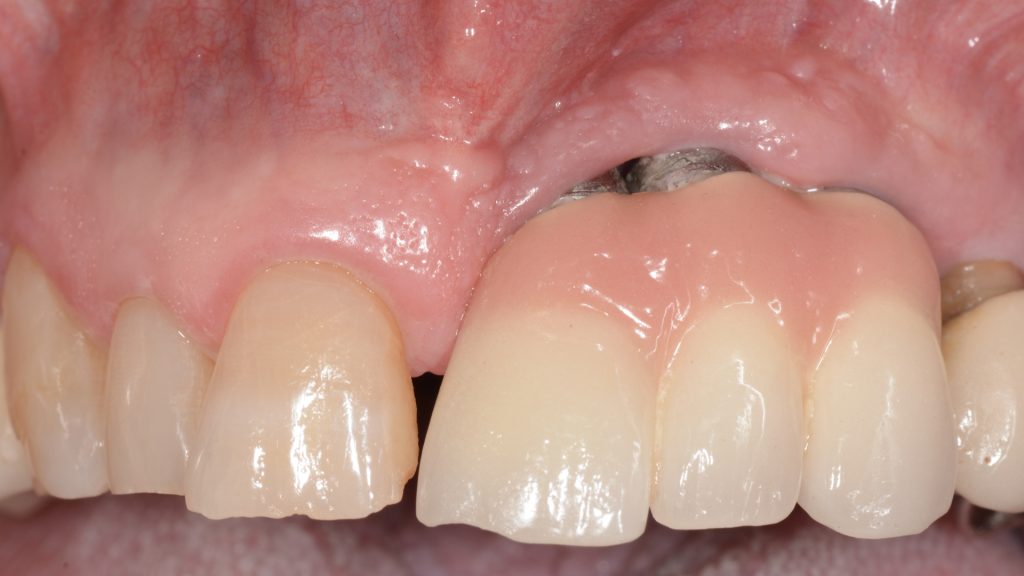

A la exploración clínica presenta implantes en posición de 21, 22 y 23 con una prótesis ceramo-metálica cementada con encía rosa donde se pueden apreciar las superficies de los implantes expuestas al medio oral (Figura 1).

- Se realizó una primera intervención quirúrgica en la que de inicio se realizó la retirada de la prótesis cementada y la explantación de los implantes en posición de 21, 22 y 23 y se realizó un injerto de tejido conectivo para sellar los lechos de los 3 implantes recién explantados (Figura 3).